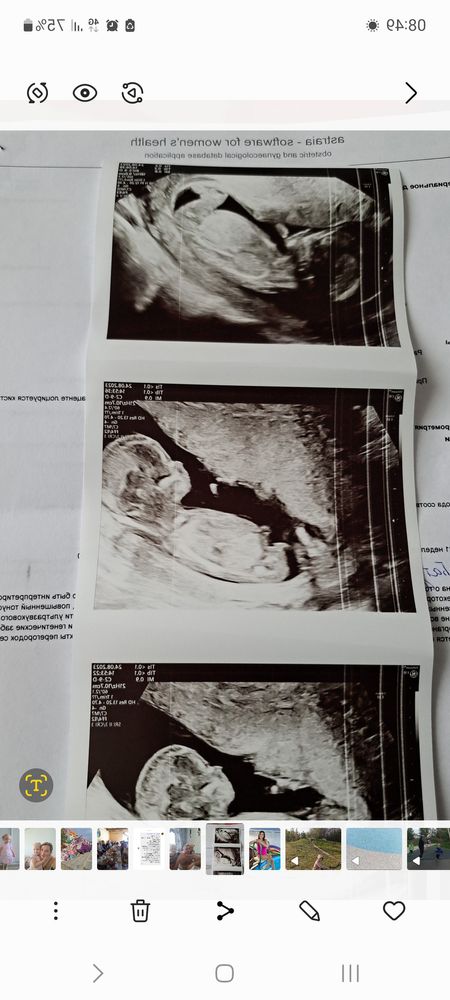

Девчонки привет!Как думаете по фотке кто мальчишечка?Этот шарик это бугорок?Или фотка не точная и это не бугорок.Врач сказала 100%мальчик.на фото 12нед6дней.С дочей ошиблись с полом даже на 2скрин.вот и думаю как она так точно сказала может опять ошиблись😊😊😊😊.С сыновьями на 2скрин фотки прям яички и писюн давали фотки.Подождем 2скрин немного осталось.но кружочек уже поставила😊😊😊